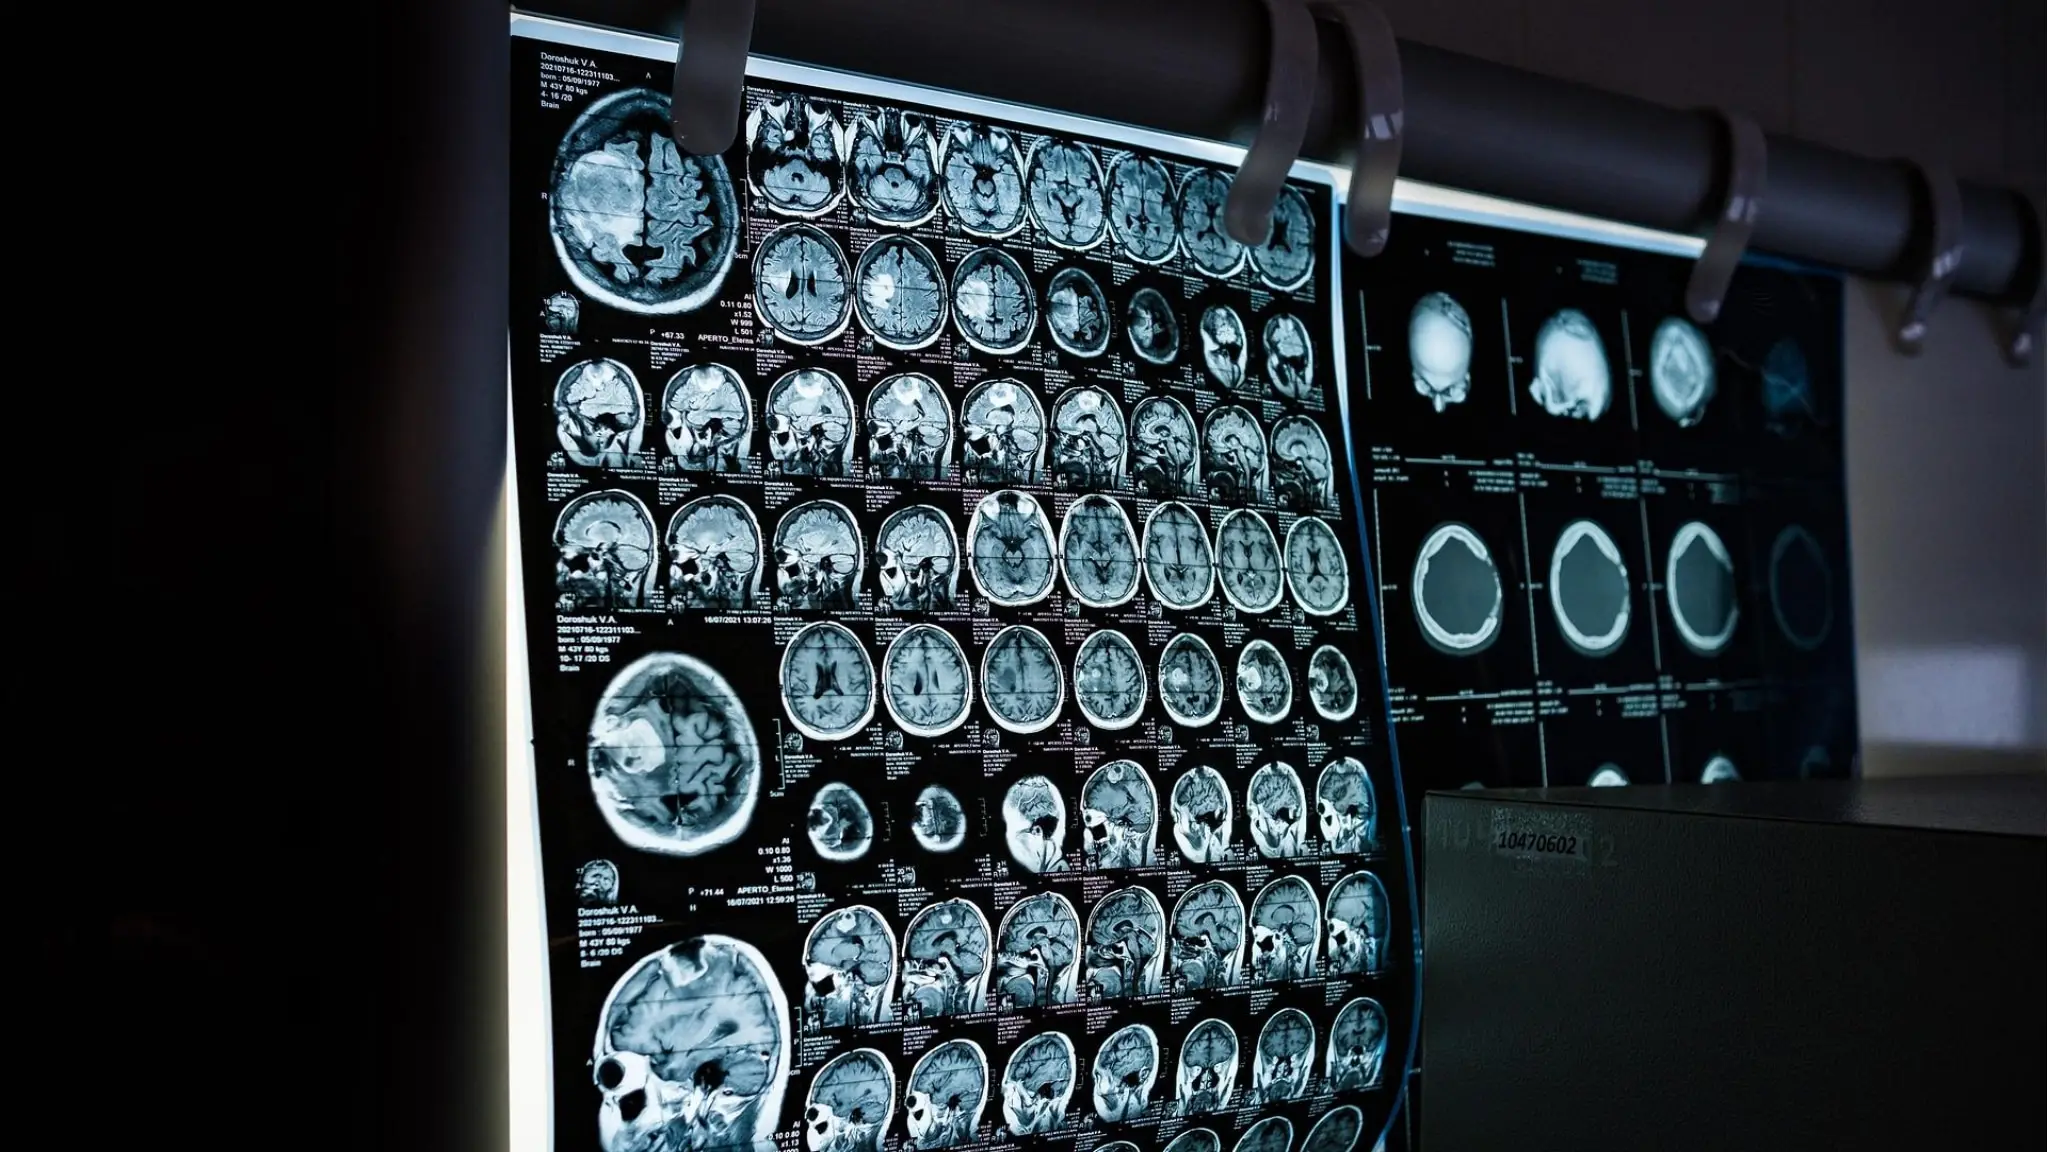

Cos'è il glioblastoma che ha colpito Sophie Kinsella. In italia 1.500 nuovi casi ogni anno

La patologia che colpì anche Nadia Toffa. E' la terza causa di morte per cancro nei maschi over 50